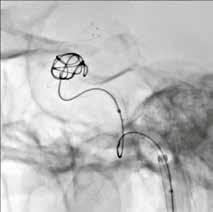

Wenn Neuroradiologen beispielsweise intrakranielle Aneurysmen mit dem endovaskulären Coiling-Verfahren behandeln, benötigen sie Sichtkontakt zur Läsion. Je besser sie die feinen, über einen Mikrokatheter in das Aneurysma vorgeschobenen Platinspiralen, die sogenannten Coils, sehen, desto präziser

HD-Flachdetektor

und zügiger können sie diese im Aneurysma packen und dessen Innenwand abdecken. Häufig muss die entfaltete Platinspirale zusätzlich noch durch einen Stent mit sehr feinem Drahtgeflecht gestützt werden, der ebenfalls genau zu platzieren ist.

Durch die Vergrößerungsmöglichkeit im HD-Modus können diese kleinen

Devices und Gefäßstrukturen auf dem Monitor klar dargestellt werden. Somit ist auch der Behandlungsfortschritt genauer nachvollziehbar. Der HDFlachdetektor funktioniert in diesem Zusammenhang wie ein Mikroskop für den Neuroradiologen. Es leuchtet ein, dass die HD-Technologie daher zu besseren Behandlungsergebnissen und höheren Überlebensraten führt.

Klinischer Fall: 11 mm Kavernöses Karotisaneurysma rechts; Behandlung mit LVIS-Blue-Stent und Coils; Bildgebung mit lateralem HD-Flachdetektor, 6 cm x 6 cm FOV, Fluoro-Modus.

Bildgebung mit Standard- und HD-Flachdetektor.

Die Bildqualität ist herausragend. Die Pixeldichte unseres HD-Flachdetektors ist so hoch, dass ein Detektorsichtfeld (englisch: field of view) der Größe von 8 cm x 8 cm auf einem 19-Zoll-Monitor bildschirmfüllend in nativer Auflösung dargestellt wird. Ohne an Bildqualität zu verlieren, sind native Vergrößerungen bis zu einem Detektorsichtfeld von 4 cm x 4 cm möglich. Im Vergleich dazu können Standard-Angiographiesysteme nur bis zu einem Detektorsichtfeld von ca. 8 cm x 8 cm nativ vergrößern. Das auf dem oben genannten Monitor angezeigte native Bild hätte dann nur eine Größe von einem Viertel der Displayfläche. Für die bildschirmfüllende Darstellung müssten die angezeigten Detektorpixel auf die doppelte Größe „aufgebläht“ werden, was natürlich mit einem Verlust an Bildqualität einhergehen würde.

Der Trend geht zur Behandlung immer kleinerer Gefäße und Gefäßanomalien. Dafür werden immer kleinere Devices verwendet und eine dementsprechend höherwertige Bildgebung wird benötigt. Die HD-Technologie eröffnet daher grundsätzlich mehr Behandlungsmöglichkeiten, gerade bei neurovaskulären Eingriffen. Die Manipulation von Mikrokathetern im Gefäßbaum vereinfacht sich. Dabei ist nochmals zu betonen, dass der HD-Modus für die dynamische Bildgebung verfügbar ist. Der Kliniker kann also die Coils und feinen Stentstrukturen in HD und Echtzeit sehen. Insgesamt kann hochpräzise interveniert und der Einsatz von offener Chirurgie noch länger umgangen werden.

Die Faktoren zur höheren Vergrößerung bedeuten doch zugleich auch eine höhere Dosis für den Patienten? Das könnte man vermuten. Es ist jedoch einerseits so, dass die HD-Unterstützung variabel einsetzbar ist, also nur bei Bedarf zugeschaltet wird, während das System sonst im Normalmodus arbeitet. Andererseits kann mit HDUnterstützung die Dauer des gesamten Eingriffs signifikant verkürzt werden, weil der Kliniker eine bessere Sicht auf

das Geschehen hat. Aufgrund der geringeren Durchleuchtungszeiten und der geringen Anzahl von Strahlungsereignissen kann die Gesamtdosis daher sogar verringert werden. Erste Studien vom Gates Vascular Institute haben für neurovaskuläre Interventionen gezeigt, dass bei Nutzung der HDTechnologie die Behandlungsfälle mit einer Patientenhautdosis über 1 Gray von 78 auf 12 Prozent und die Eingriffszeiten um 11 Prozent reduziert werden konnten. Nicht zu vergessen, dass die HD-Technologie gemeinsam mit der DoseRite Dosisreduktionstechnologie eingesetzt wird.